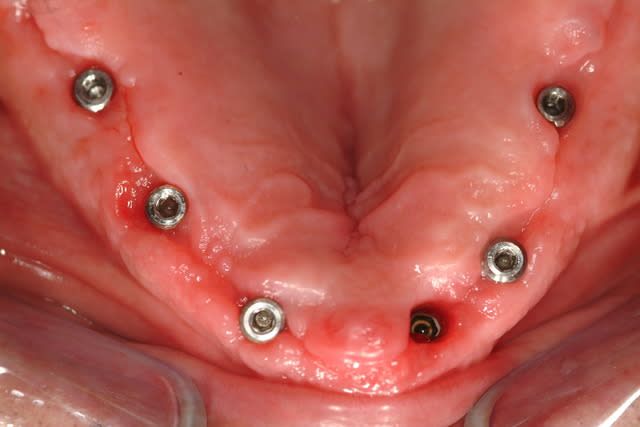

J'ai abandonné la MCI au maxillaire sur 4 implants c'est trop risqué.

Aucun filet de secours, je préfère avoir au moins 6 implants bloqués à min 30 Ncm, pour mettre en charge un maxillaire complet.

A la mandibule 4 implants, ça fonctionne très bien, j'en ai fait beaucoup aussi.

Voici déjà un cas avec 6 implants maxillaire et mandibulaire.

Le bas est pour le moment en résine, on doit passer plus tard à un bridge vissé sur armature métallique.